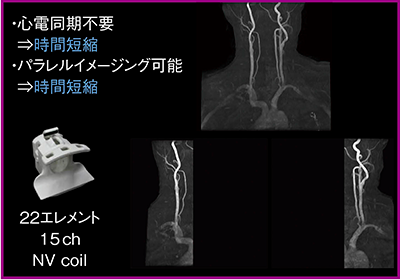

●頭頸部撮像

頸部撮像では,22エレメント15chのNV coilを用いて広範囲MRAを撮像している(図2)。感度域が広く,大動脈弓部を含めても頸動脈を十分に描出することができる。心電図同期も不要で,パラレルイメージングが可能なため,撮像時間の短縮が可能だ。頭頸部検査もNV coilを用いることで,頭部MRIから頭頸部MRAの一連の撮像を30分以内で終えることができる。

図2 広範囲MR